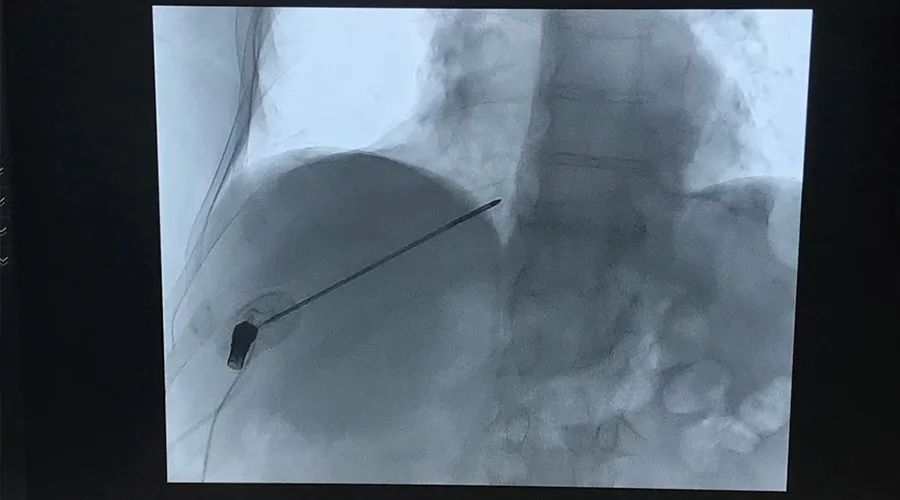

术中影像资料

肿瘤位于肝脏,直径为1.5cm。主刀医生使用赛诺微SS-MWA-1531C微波天线对肿瘤进行了单针消融(75w,5min)。“你可以看到,微波天线在X光透视下,针体轮廓非常清晰,显影非常好”,主刀医生指着影像图片对我们说道。手术顺利完成后,医生向我们表示他对Dophi™ M150E微波消融系统的临床表现和消融结果非常满意。“Dophi™ M150E微波消融系统的表现完全超出我的预期!它非常可控,非常精准,手术非常成功!”